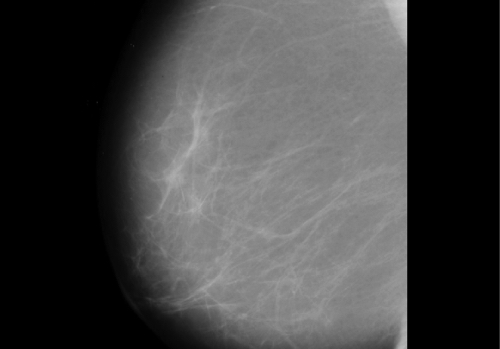

La mamografia és la prova més eficaç per la detecció precoç d’un càncer de mama. Amb tot, segueixen havent-hi falsos positius, és a dir, casos en què la intepretació de la mamografia condueix a un error de diagnosi i detecta un tumor que en proves posteriors es demostra inexistent perquè els mètodes actuals per interpretar els resultats d’aquesta prova encara no són 100% eficaços.

Precisament amb l’objectiu de millorar la lectura de les mamografies i al seu torn, els casos de falsos positius, un grup d’investigadors de la Universitat Rovira i Virgili (URV) ha ideat un programa informàtic d’anàlisi d’imatges que permet un encert del 99% en alguns casos.

L’estudi s’ha fet a partir de veure l’efecte de diversos mètodes d’anàlisi de les imatges a les quals s’ha aplicat diverses tècniques -anàlisi de resolució de píxels, algoritmes de processament de la imatge o normalització de dades-. “Mentre que els radiòlegs estan generalment satisfets amb els sistemes de diagnosi assistida per ordinador (CAD per les seves sigles en anglès) en la detecció de microcalcificació agrupada o concentrada, tenen menys confiança en la detecció de massa. La queixa més comuna entre radiòlegs és precisament que els sistemes CAD porten a un nombre elevat de falsos positius”, recull l’article.